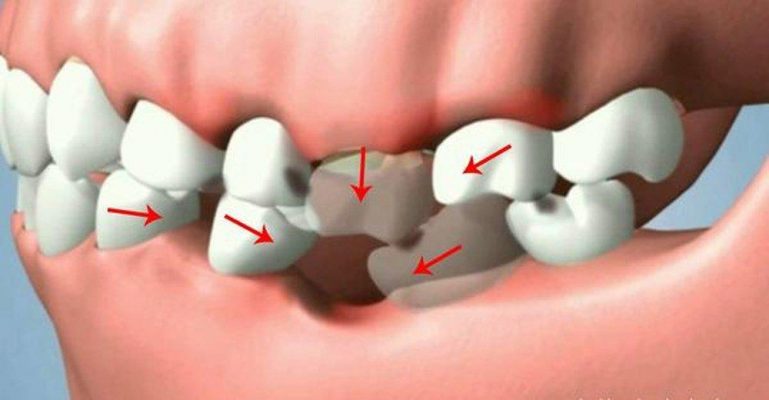

– Các răng thật dùng làm trụ để mang răng mất sẽ bị mài nhỏ đi trong kỹ thuật làm cầu dẫn đến :Răng trụ có thể bị ê buốt hoặc ảnh hưởng đến tủy răng sau này. Răng trụ có thể phải được chỉnh sửa như chữa tủy, làm thấp đi,…để phù hợp với yêu cầu của một răng trụ. Làm cầu răng sứ chỉ thay thế được phần răng ở trên chứ không thay thế được chân răng.

– Phương pháp này hoàn toàn không ngăn ngừa được tình trạng tiêu xương hàm, lợi co lại do mất răng. Lâu dần sẽ làm cho cầu răng mất tính thẩm mỹ. Việc tiêu xương hàm, tụt lợi ở vị trí răng mất cũng ảnh hưởng đến các răng trụ và làm cho các răng trụ yếu đi nếu xương hàm bị tiêu quá nhiều gây hở chân răng trụ.